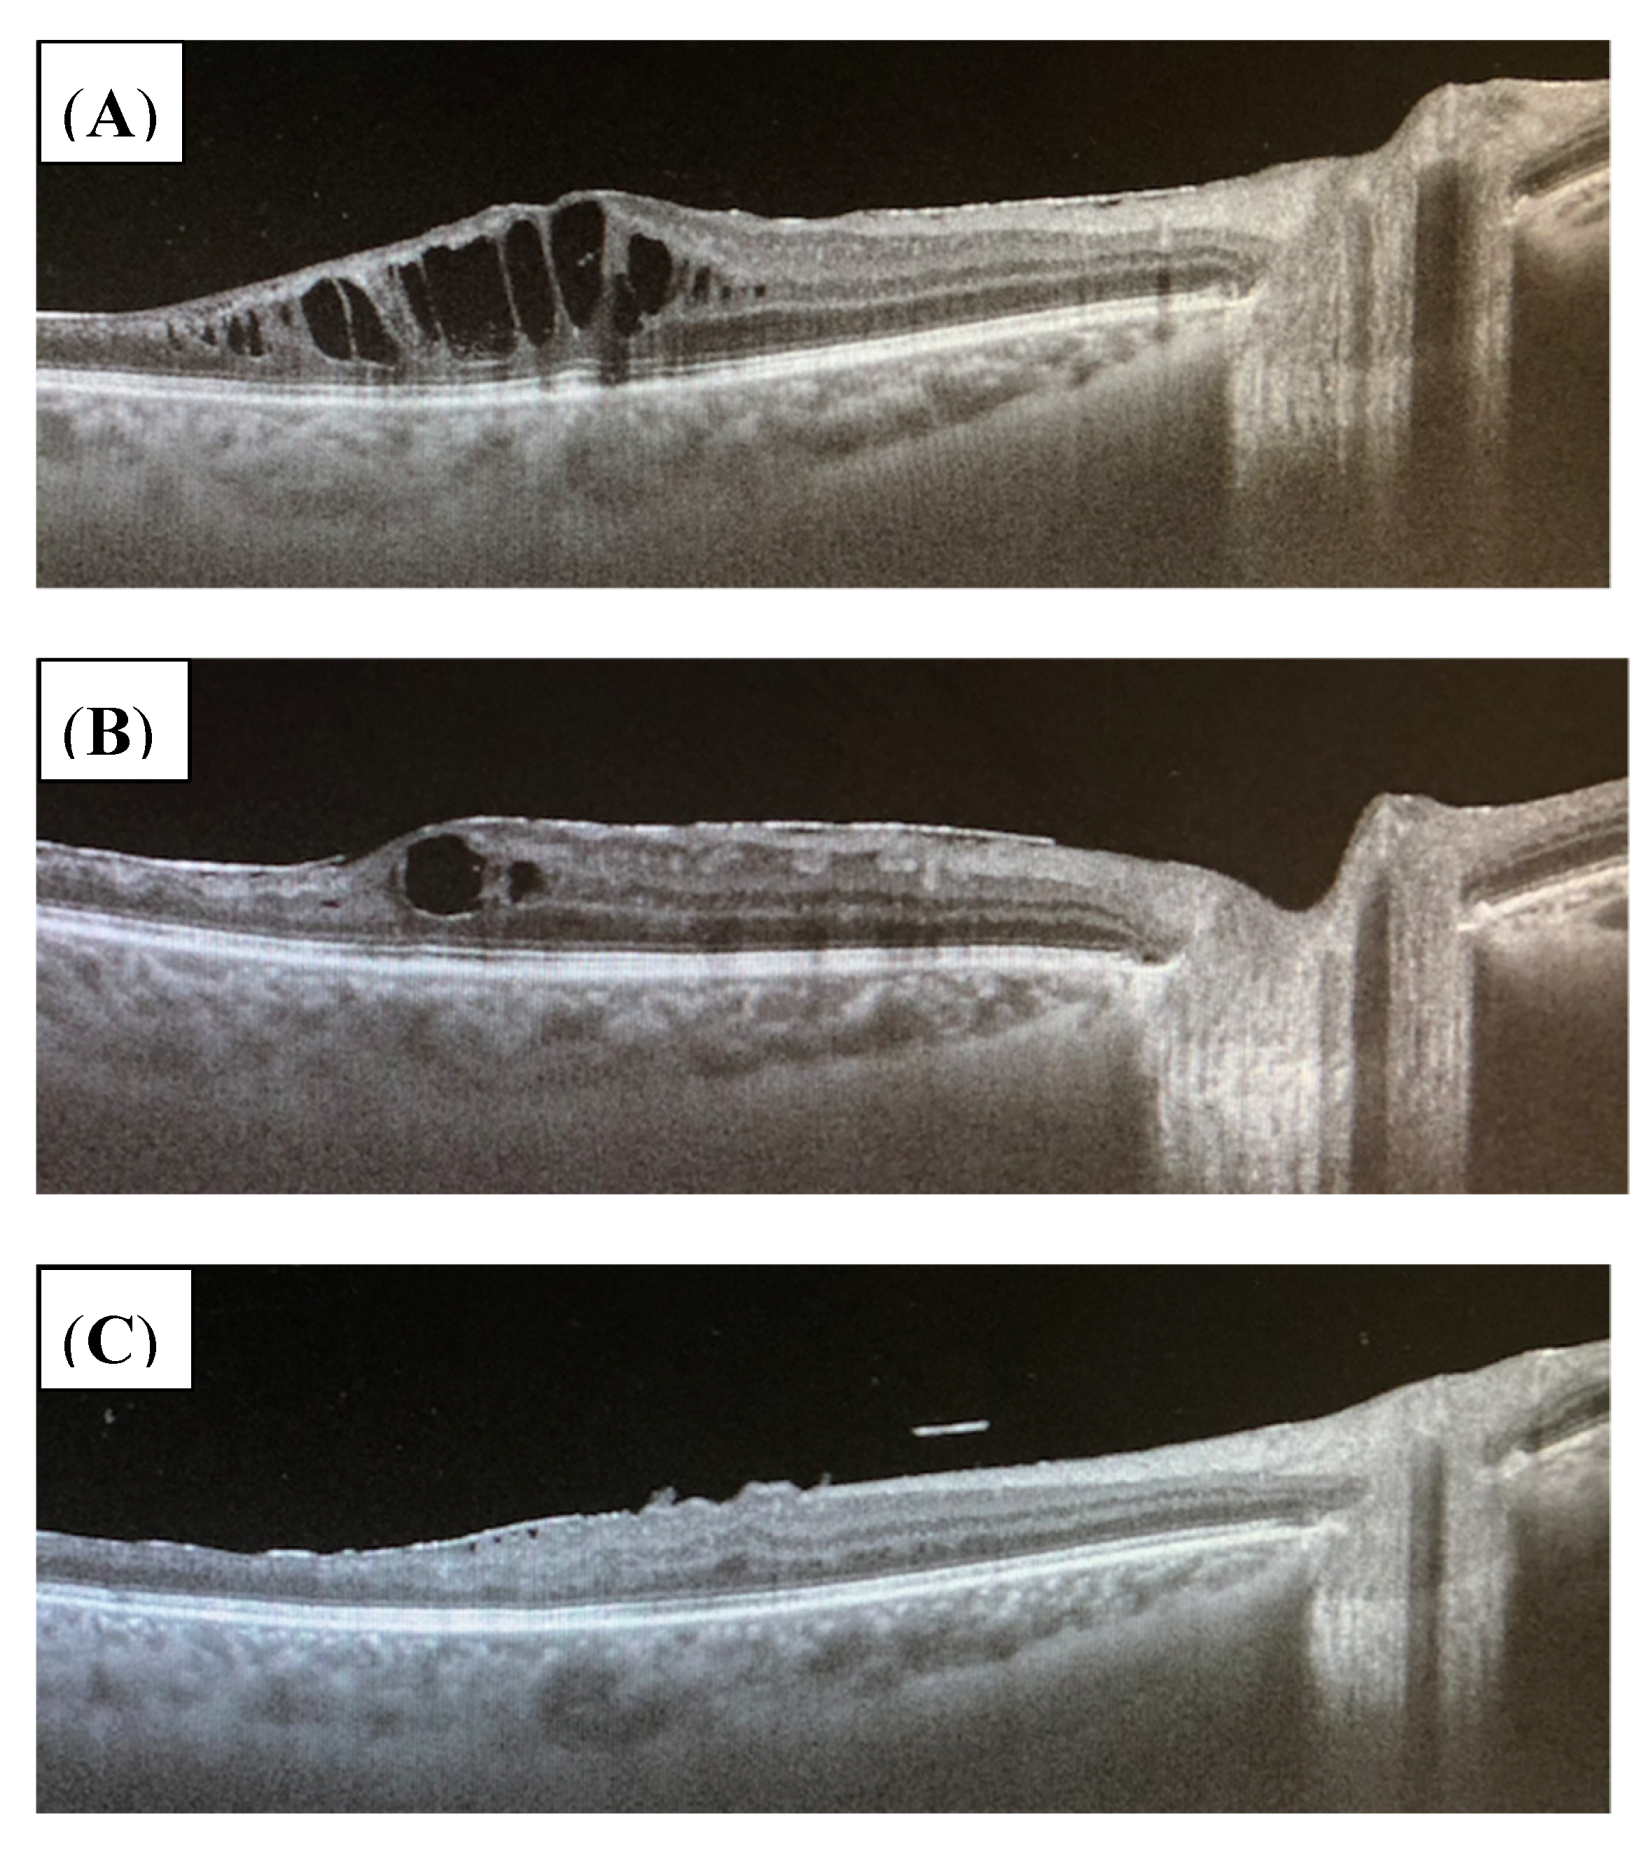

3.3.2. Uveitic Macular Edema